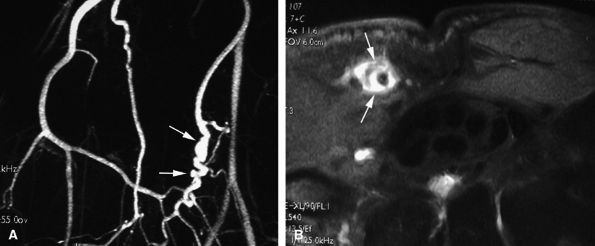

-

Nodular or tubular enhancement may be seen after gadolinium administration. MRA is complementary to standard MR studies, providing precise details of the angiographic appearance of the malformation (Fig. 11.78). MRA of the fingers is technically challenging because of the small caliber of blood vessels and their changing orientation. The MRA technique that is most suited to the fingers is a 3D coronal acquisition after gadolinium administration. This rapid technique (requiring less than 30 seconds for acquisition) yields high spatial resolution and is not dependent on vessel orientation. Injection of a gadolinium test dose allows precise determination of maximum arterial enhancement.180 Temporal resolution remains inferior to DSA.4

better angiographic assessment of the venous malformation than arteriography alone.116

FIGURE 11.78 ● Venous malformation. (A) Axial post-contrast fat-suppressed T1-weighted image showing vascular malformation invading the fourth intermetacarpal space and the fifth metacarpal (arrows). (B) MR angiogram of multifocal vascular malformation with a distal extension toward the lateral aspect of the fifth finger (arrows).